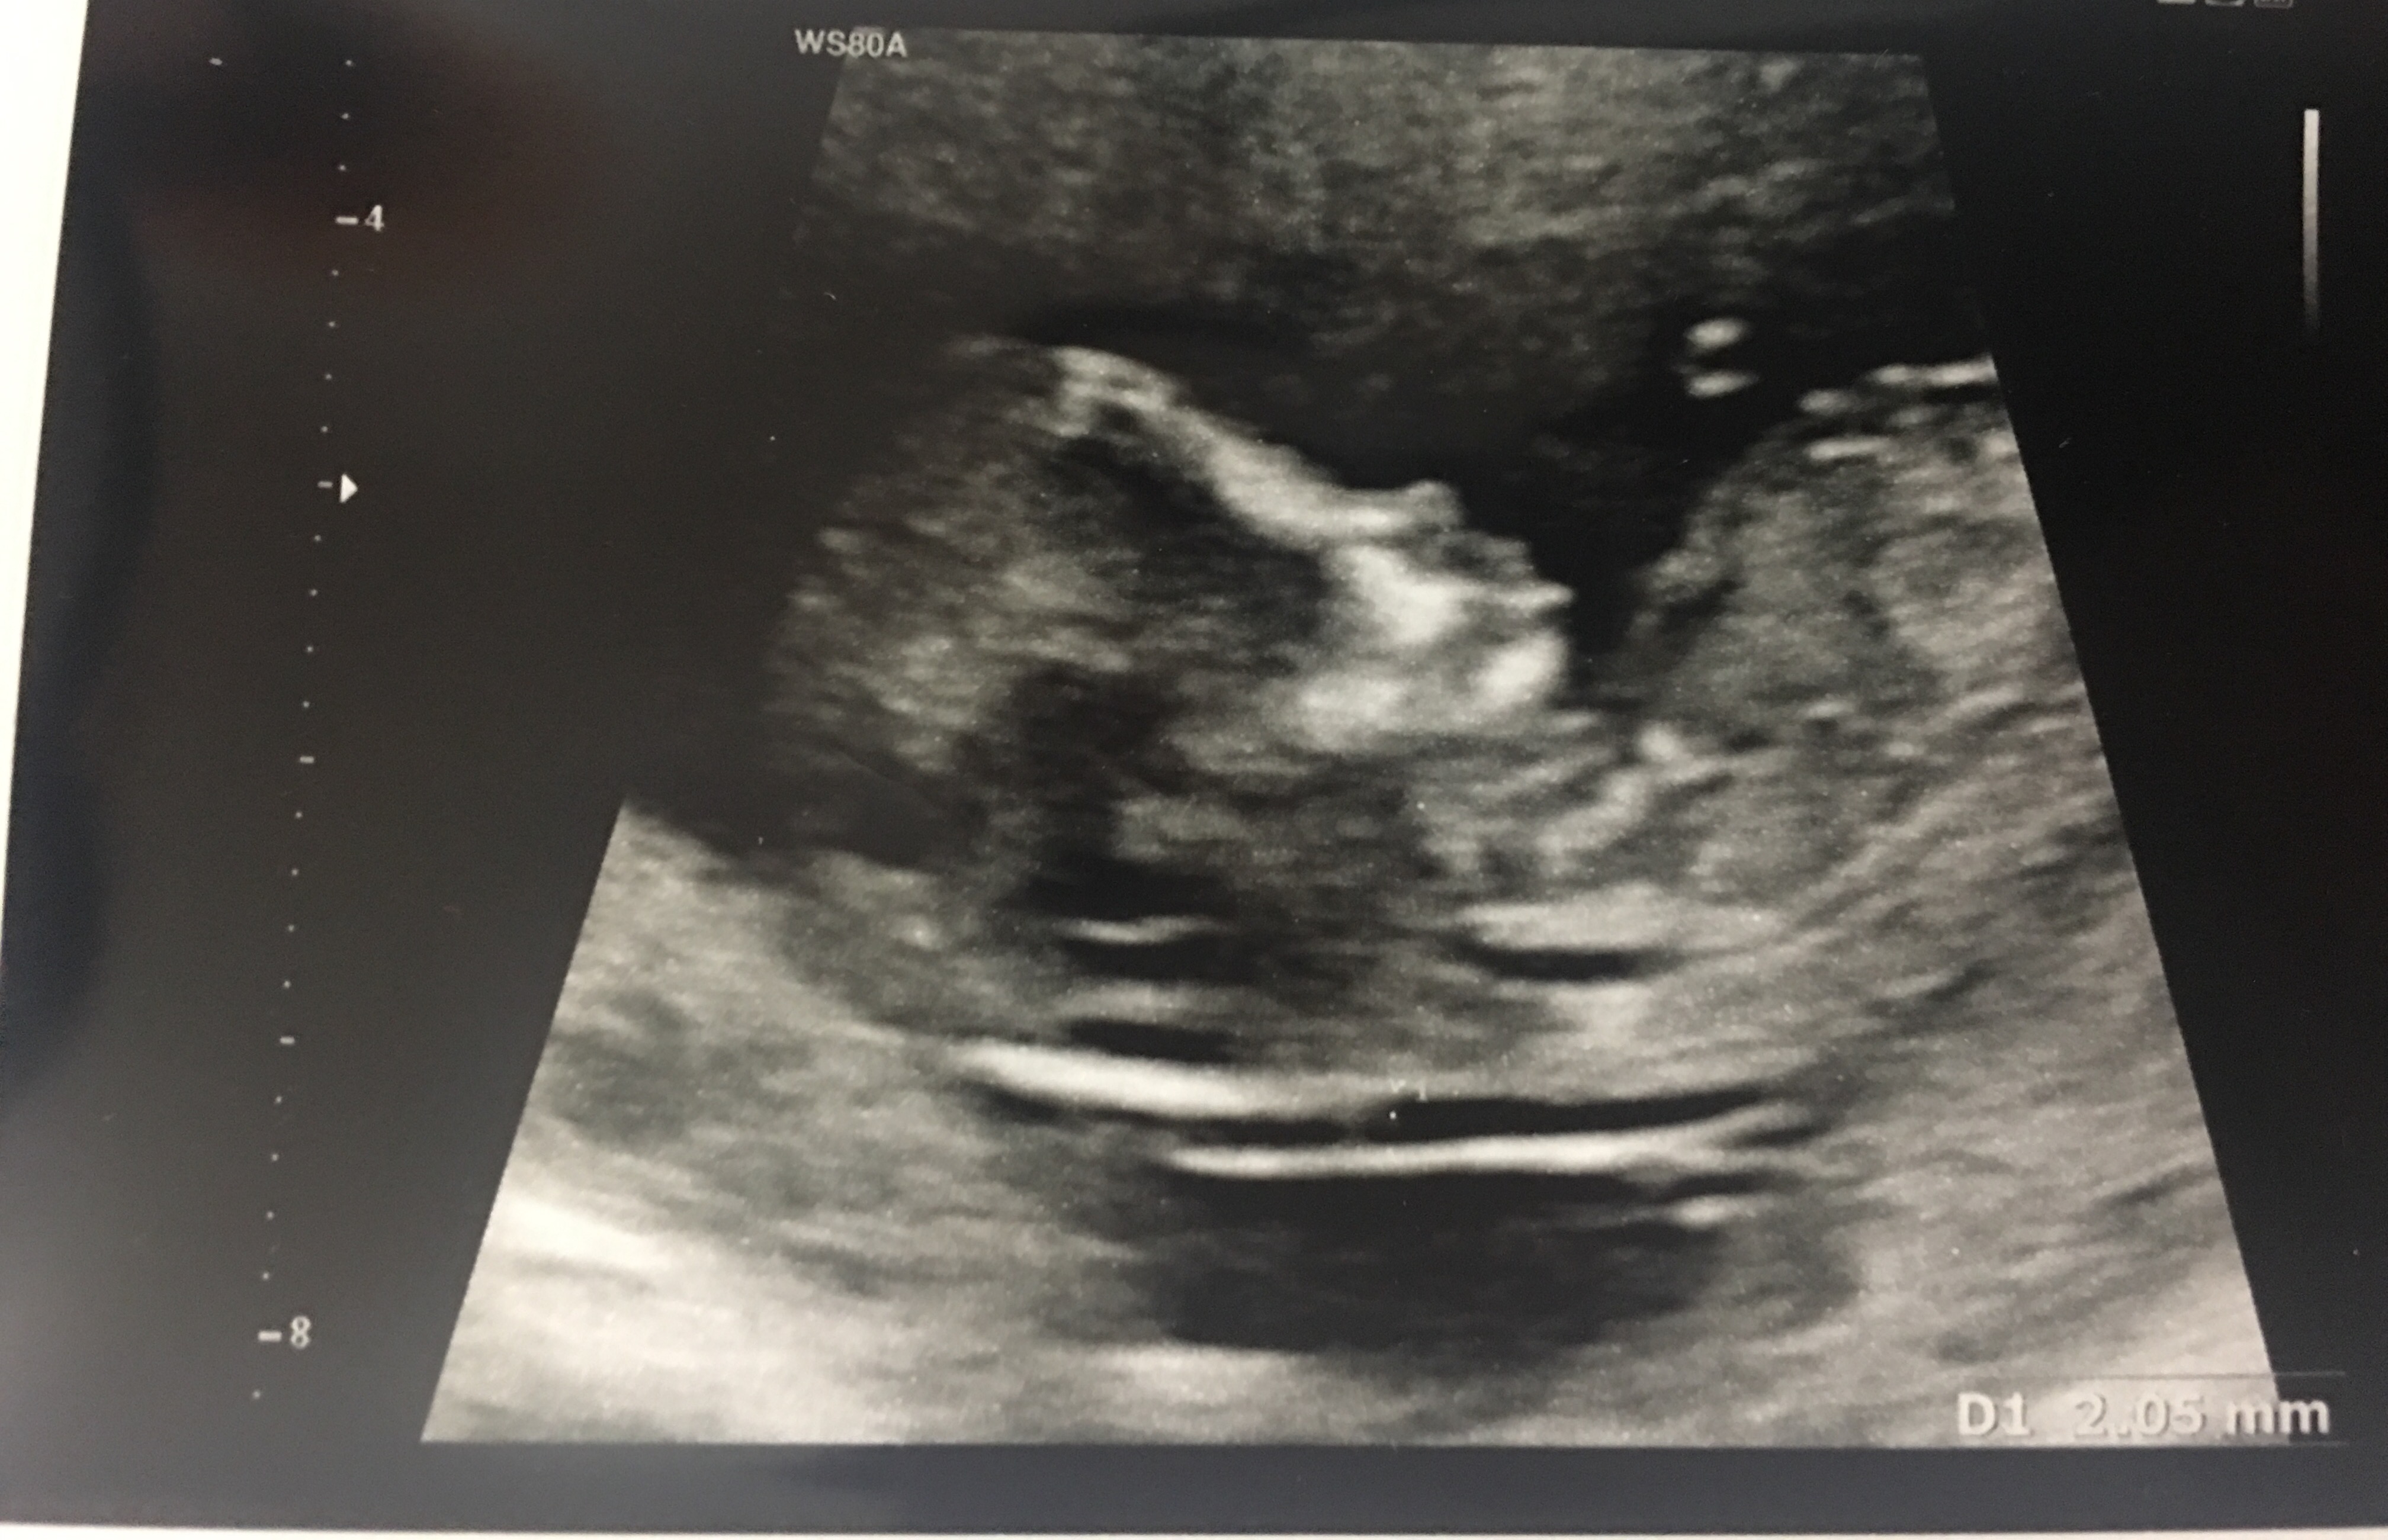

سونو گفته ۹۰درصد دختره میخوام ببینم چقدر صحت داره😥

عزیزم معمولا درسته....به من آن تی گفت احتمالا پسر....پسر شد.. البته اگر جای معتبررفته...چون از ستون فقرات وحمجمه وایناتشخیص میدن...دستگاهشونم پیشرفته..بنظرم درسته

😔😔😔چی بگم میگن صورتش وچونش بهددختر میخوره

[QUOTE=101815989]عکس ان تی شمارو دیدم منم مطمئنم دختره[/QUOTEشمام شبیه اینه

منم سر. غربالگری اول بهم گفت از مدل لگنش دختره

ولی سر غربالگری دومی پسر. بود

فعلا صبر گفت ان تی صد در صد. نیست